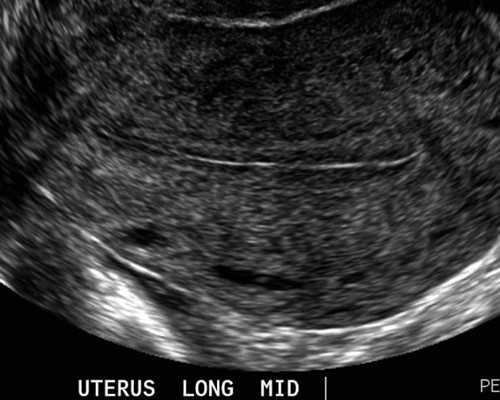

女科:促排卵-指导受孕、经阴B超卵泡监测、复发性流产免疫治疗、超声子宫输卵管造影术、无痛宫腔镜检查术、卵泡穿刺术、子宫动脉血流测定、多胎妊娠减灭术等。